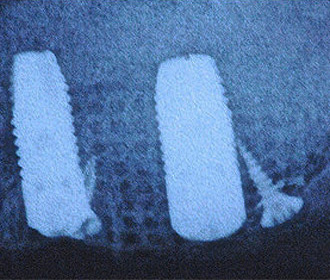

インプラント治療例

外傷による上顎左右11抜歯後即時インプラント+インビザライン矯正

インプラント治療時にはチタンメッシュ+人工骨による大掛かりな骨移植を行っている。

矯正治療、骨移植を伴うインプラント治療、セラミック・クラウン等による機能的、審美的治療

矯正治療、骨移植を伴うインプラント治療、セラミック・クラウン等による機能的、審美的治療

術前